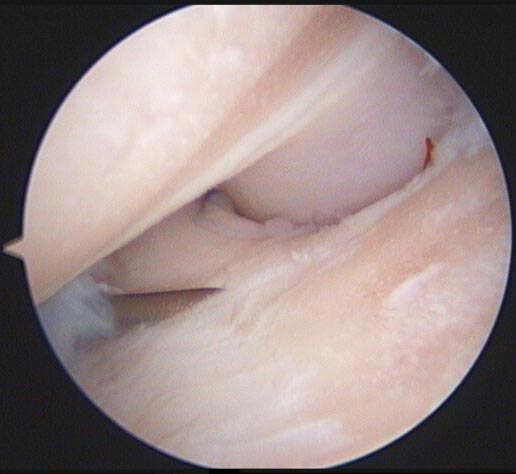

The inciting cause of OA is damage to the articular cartilage, which triggers a vicious circle of degenerative changes and inflammation.

Given the underlying cause of OA is damage to the articular cartilage, OA may be initiated when the rate of damage exceeds the rate of repair. It may be useful to consider how OA might be classified.

Normal loading of an abnormal joint is common in vet patients due to the myriad of developmental disorders that exist in certain popular breeds. These cause an incongruence between the joint surfaces, resulting in the force being focused on a small area of the joint.